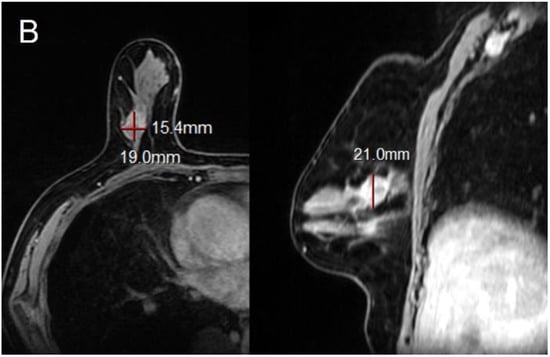

Figure 3.

78-year-old woman with invasive ductal carcinoma in right breast. (A,B) Maximal diameter by CAD, radiologist and pathology were 1.8 cm, 2.1 cm, and 1.8 cm. Both CAD-and radiologist-measured sizes were accurate, in reference to pathology. This cancer was of luminal B subtype, negative EIC at pathology and mass type on MRI (R: right, UO: upper outer).